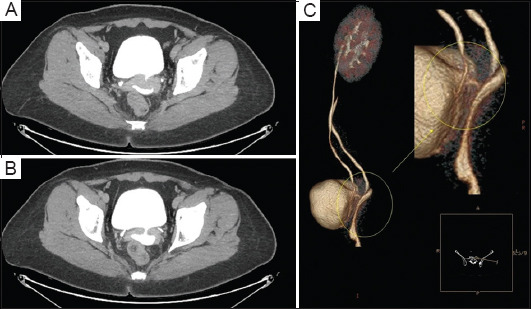

Objective: This study presented a novel approach involving a complete omental wrap for repairing a small-capacity, irreparably damaged bladder following cystotomy in a complex transvesical vesicouterine fistula repair.

Methods: Salvage repair was performed on a severely damaged bladder that had resulted from a chronic vesicouterine fistula, using an omental wrap for augmentation. The omental wrap fully enclosed the bladder to enhance its recovery. The patient had an uneventful post-operative recovery, and follow-up cystography showed a small-capacity bladder with no leakage. Extended follow-up demonstrated resolution of the patient's symptoms and an improvement in bladder capacity.